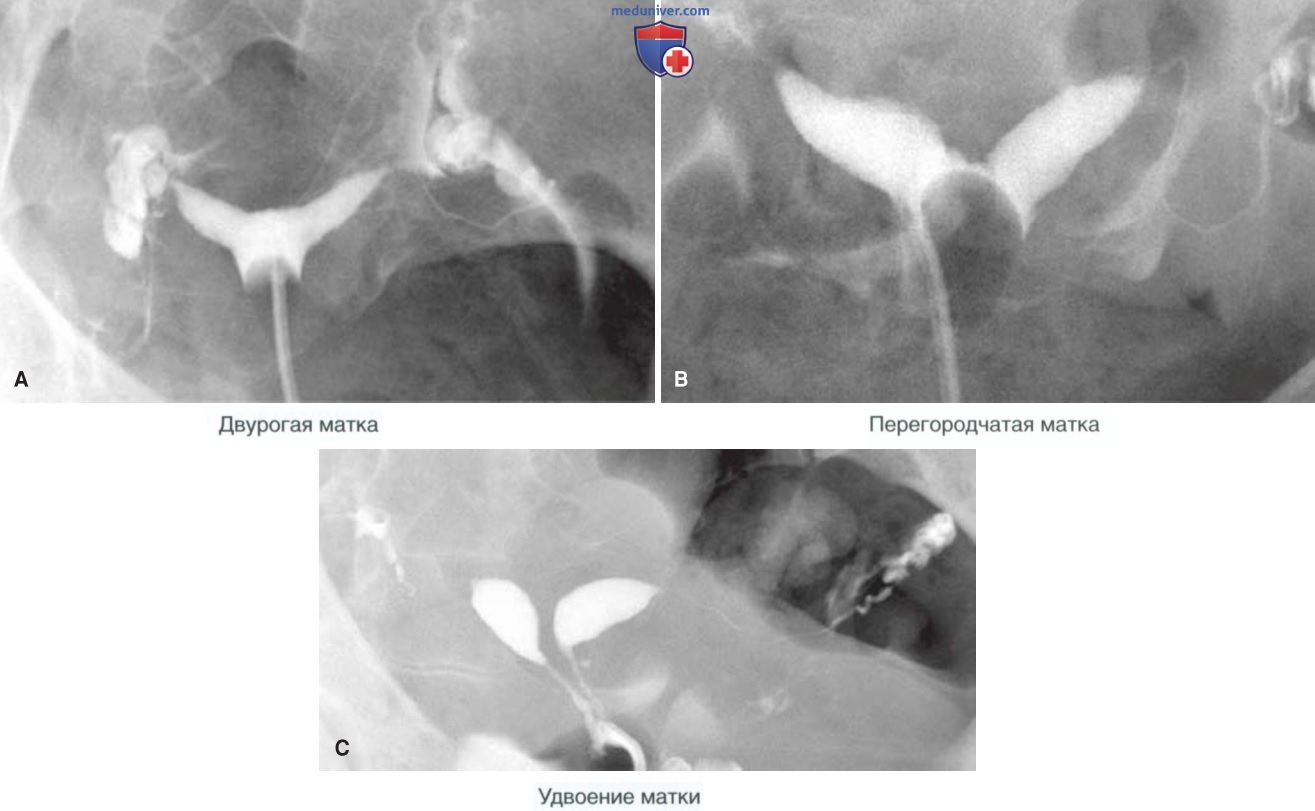

Патология две матки

Патология две матки 117 фотографий